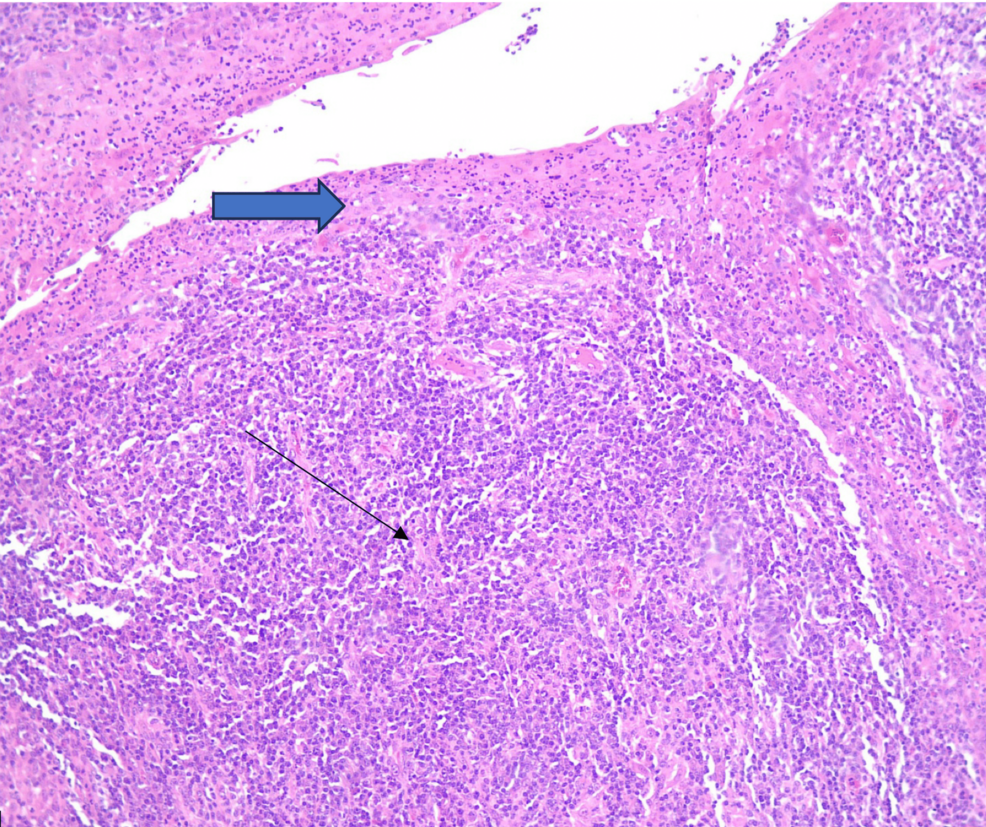

La afectación de las amígdalas en casos de sífilis es poco común y puede manifestarse como ulceración, lesiones exofíticas o un aumento del tamaño similar a una masa, imitando infecciones bacterianas, según un reciente informe de caso y revisión de la literatura publicado en Cureus.

Este estudio destaca la importancia de considerar la sífilis en el diagnóstico diferencial de inflamación o lesiones inusuales en las amígdalas.

Otro caso reportado en Cureus, publicado el 29 de marzo de 2025, documentó un caso de inflamación unilateral de las amígdalas en un hombre griego heterosexual de 52 años con sífilis secundaria. Este caso también enfatiza la importancia del diagnóstico histopatológico diferencial.